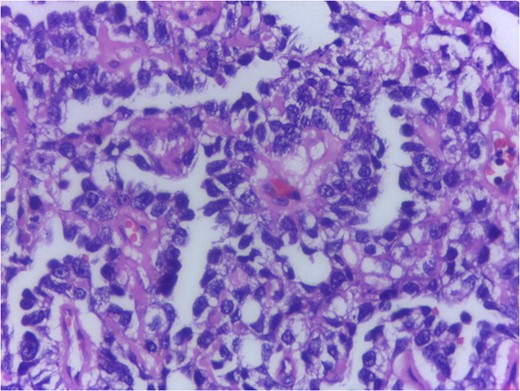

Serum markers on day of surgery were Alpha Feto Protein (AFP) 131 146 ng/ml (normal range 0–20 ng/ml), Beta subunit of Human Chorionic Gonadotropin (beta hCG) 0.5 mIU/ml (normal range < 2 mIU/ml), Lactate Dehydrogenase (LDH) 1231 U/L (normal range 0–850 U/L)

Serum markers, histopathological examination and IHC all three confirmed diagnosis of yolk sac tumour.